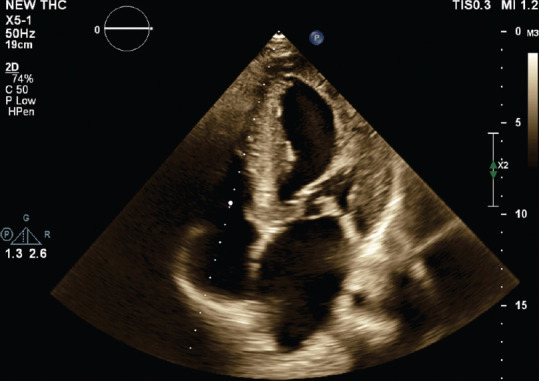

A Rare Case of Intramitral Valve Ring in the Setting of Shone Complex Diagnosed by Echocardiography.

一例通过超声心动图诊断出 Shone 复合物的罕见瓣膜内环。